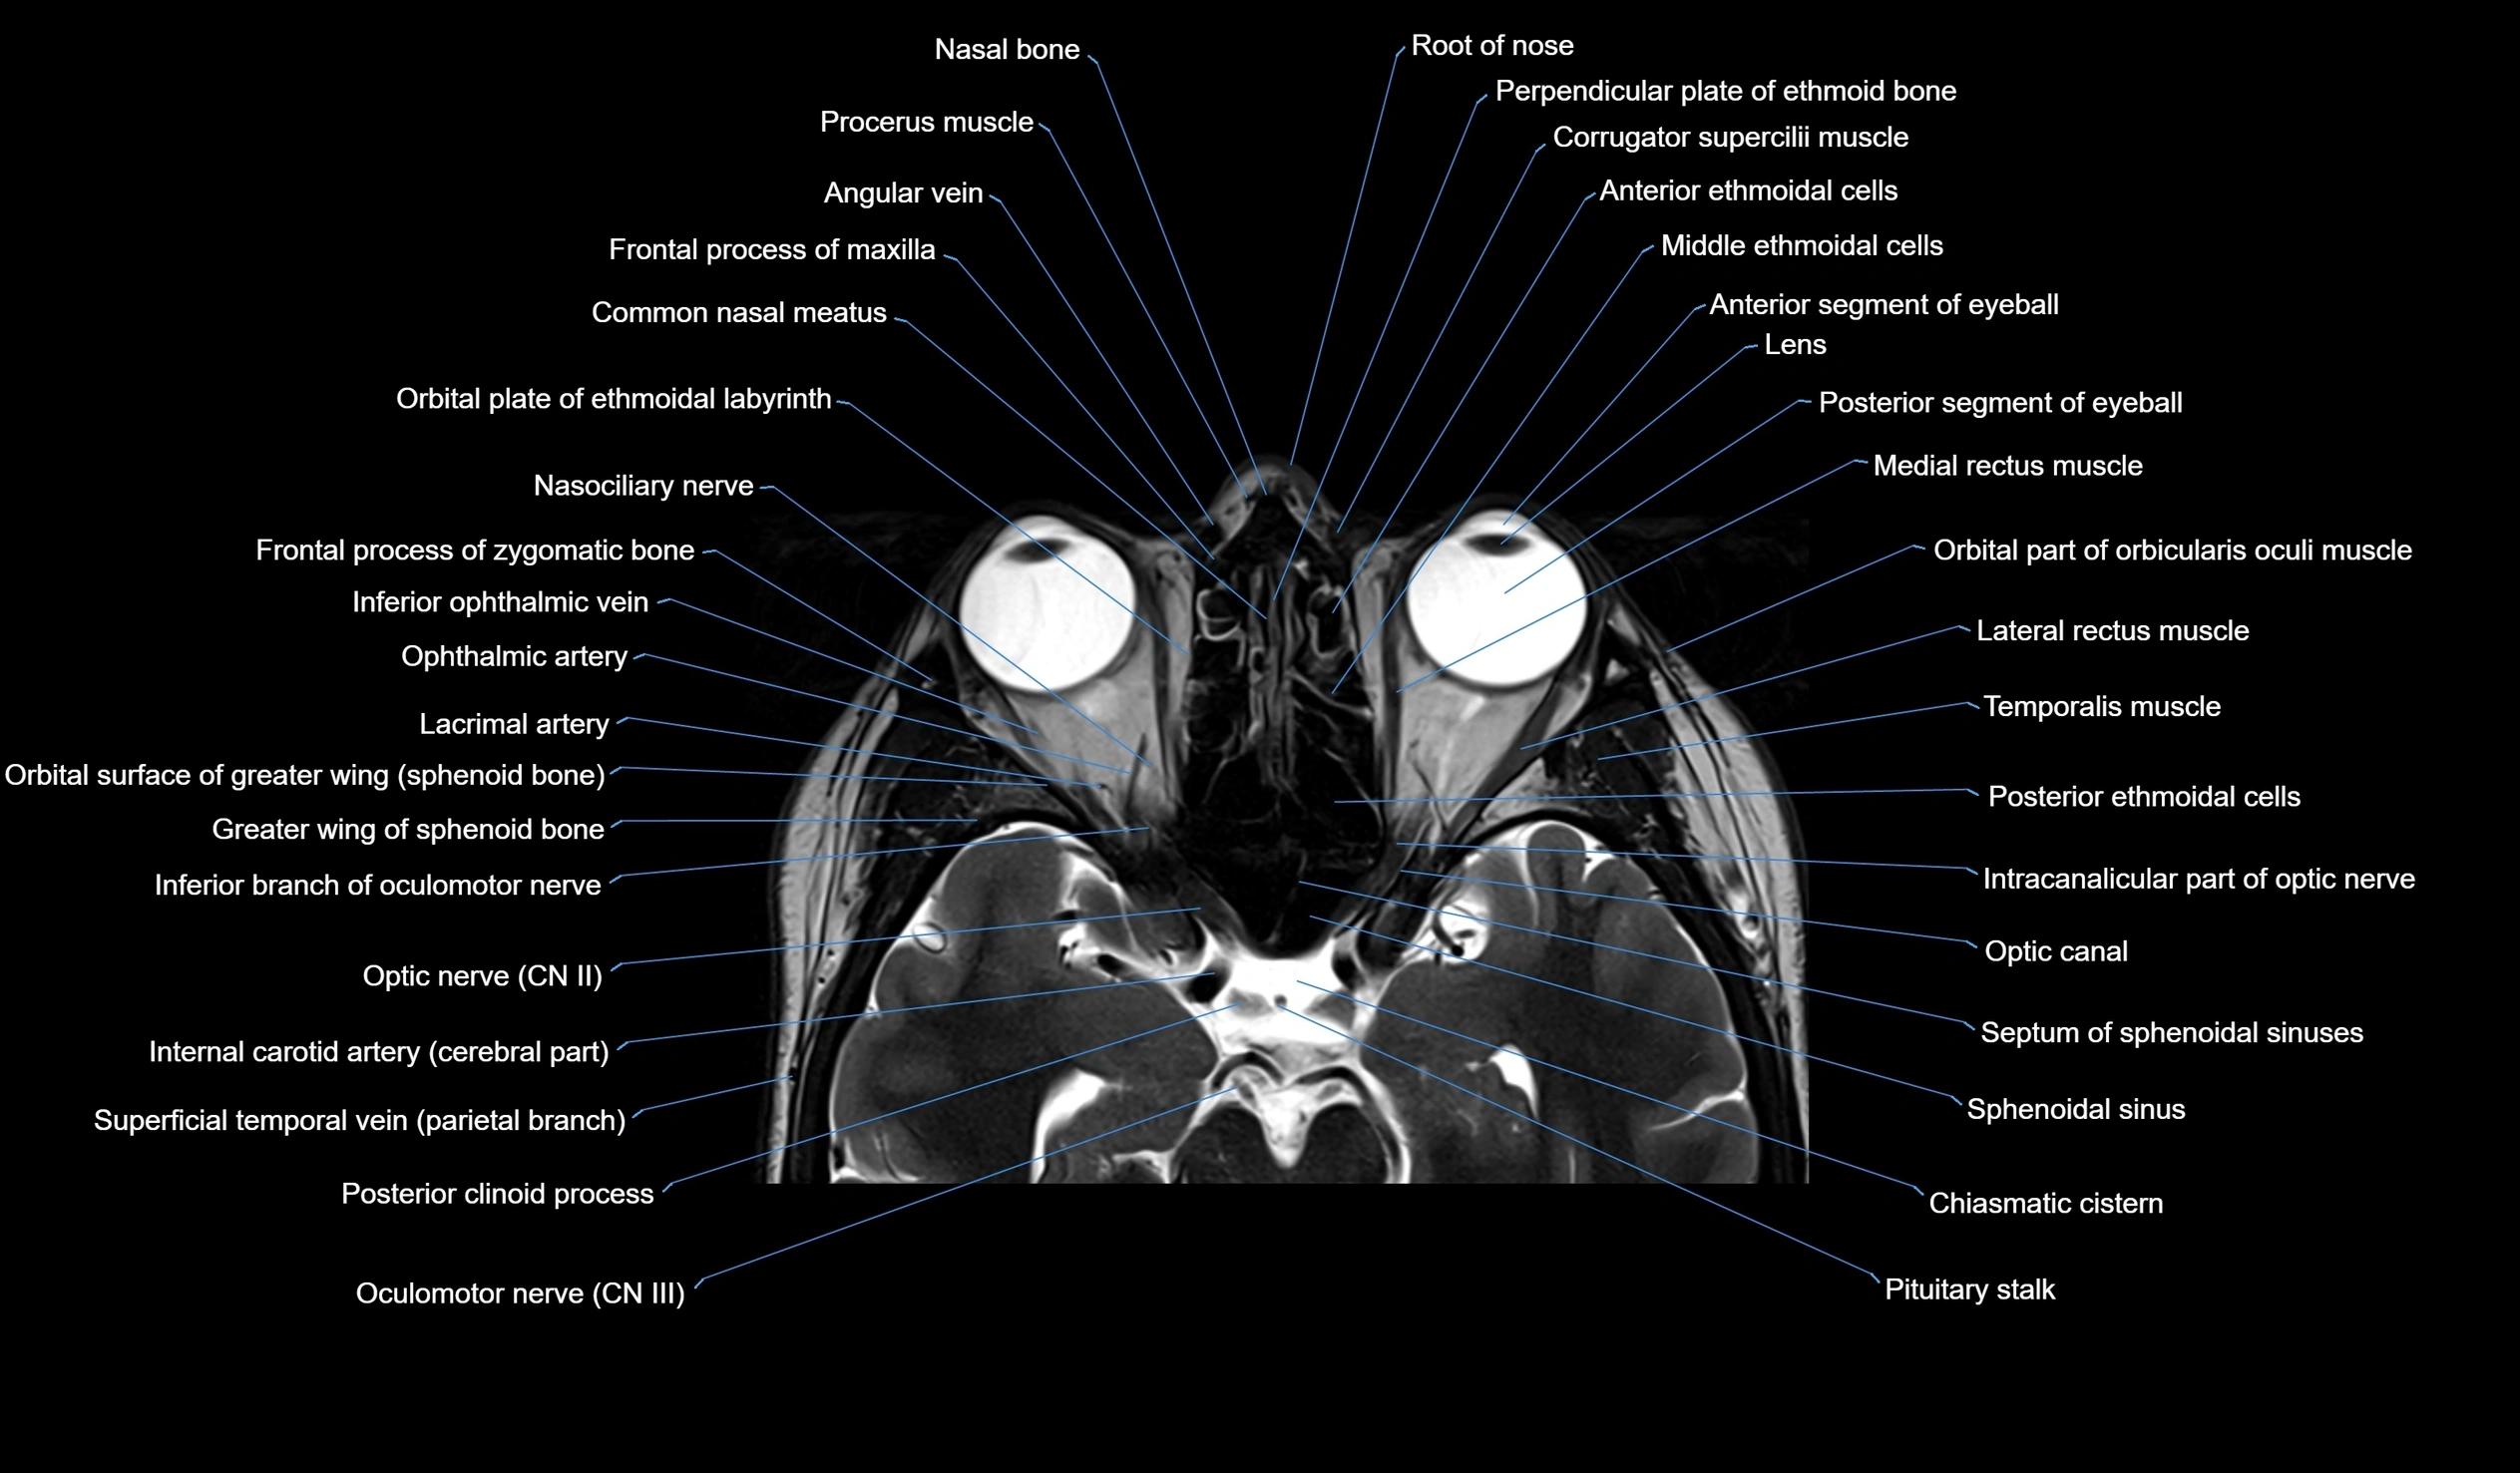

MRI images